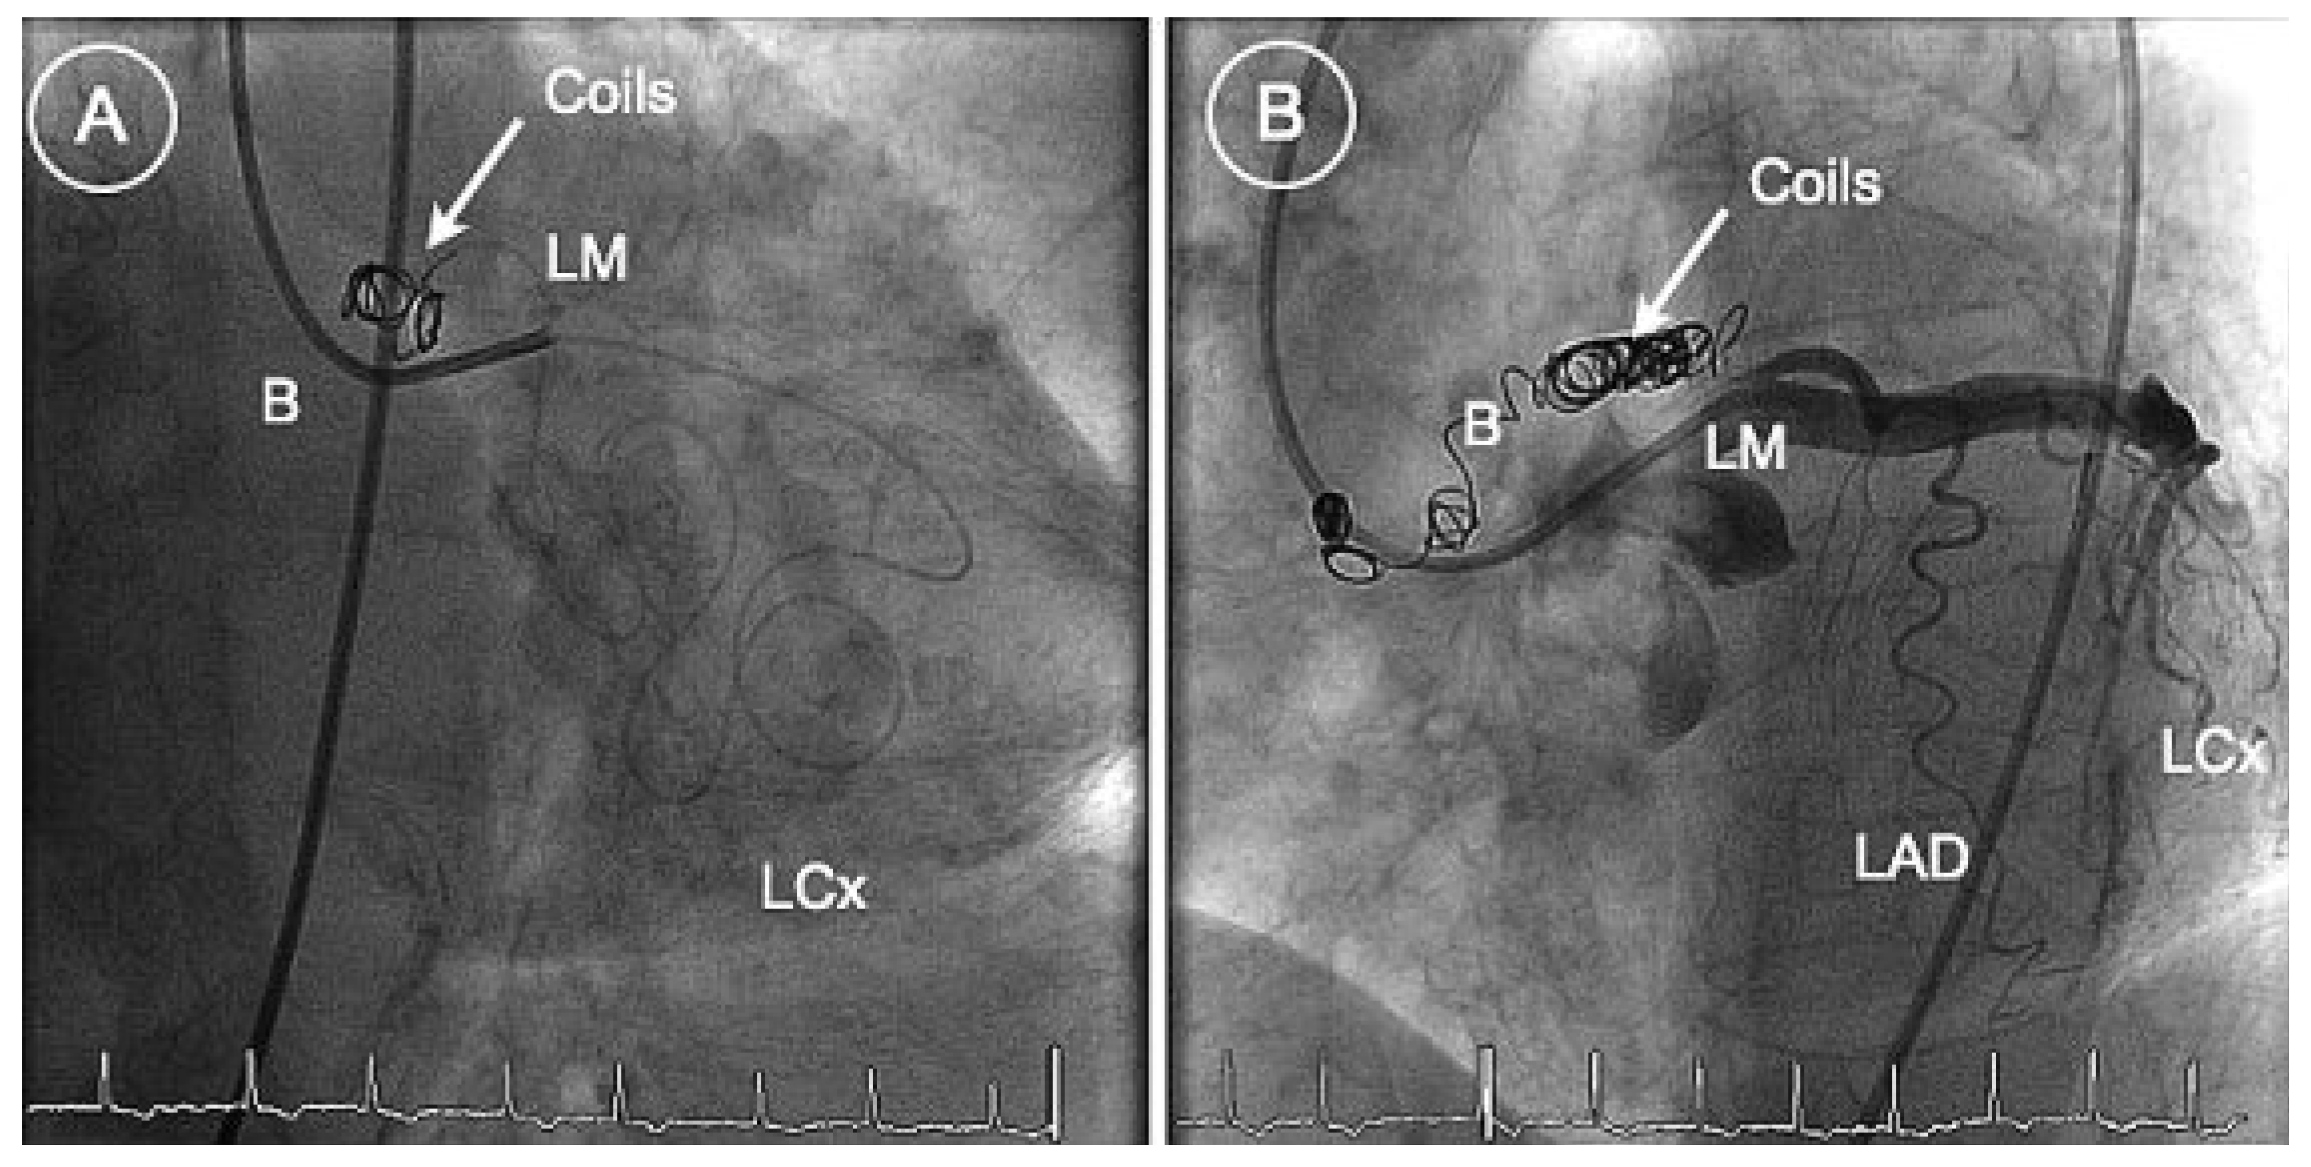

Figure 2.

RAO (A) and anteroposterior (B) caudal views showing the deployment of coils within the fistula. Successful reduction of bloodflow within the fistula (B). LM = left main coronary artery; LAD = left anterior descending artery; LCx = left circumflex artery.